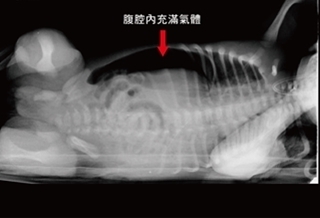

(優活健康網記者徐平/綜合報導)一名出生才2天的男嬰,因先天性血管不良,導致胃缺血缺氧而局部壞死穿孔,到院時心跳加快、呼吸急促、全身性蒼白,經X光檢查,發現腹腔內充滿氣體,醫師判斷消化系統有破洞,在切除約4/5的胃後,已經可以正常喝奶,體重也增加500公克。血壓偏低、發炎指數偏高、哭聲弱澄清醫院新生兒加護病房主任黃元韻表示,該男嬰到院時的血液循環不是很好,血壓偏低、發炎指數也偏高,出現全身性蒼白且哭聲無力微弱,腹部氣脹,必須由小兒外科緊急開刀,否則會有生命危險。澄清醫院小兒外科主任林雨利指出,男嬰腹腔中滿佈黃色的結塊,且胃部組織已破了一個洞,男嬰已呈現敗血症現象,清理出黃色結塊並將胃部切除約4/5後,才救回小嬰兒一命。胃患部薄弱 乳液脹破胃壁流到腹腔林雨利主任解釋,腹腔內的黃色結塊是嬰兒餵食奶水後與胃酸綜合後,從胃部的破洞流出,由於該男嬰先天性供給胃部的血管不良,在母胎中其胃尚未運作,一出生後胃就開始運作,有可能在缺血缺氧的胃患部已呈薄弱現象,當一開始餵乳後,乳液就脹破單薄處的胃壁,流到腹腔裡。該男嬰手術成功後,術後的照顧就交給新生兒加護病房醫護人員,黃元韻主任表示,一開始以全靜脈營養照護該男嬰,7天後再從水到奶水餵食,經住院一個月,該男嬰由原本的3000公克體重增加至3500公克而順利出院,目前該男嬰每3小時的食量已達100西西的奶水,身體健康。注意營養均衡、少量多餐黃元韻主任指出,像這樣出生2天就胃部切除4/5的嬰兒,基本上要注意營養均衡,最好的方法是少量多餐,隨著男嬰長大,胃部會再擴大,吃固體食物仍需多加注意,並且需定期回診。